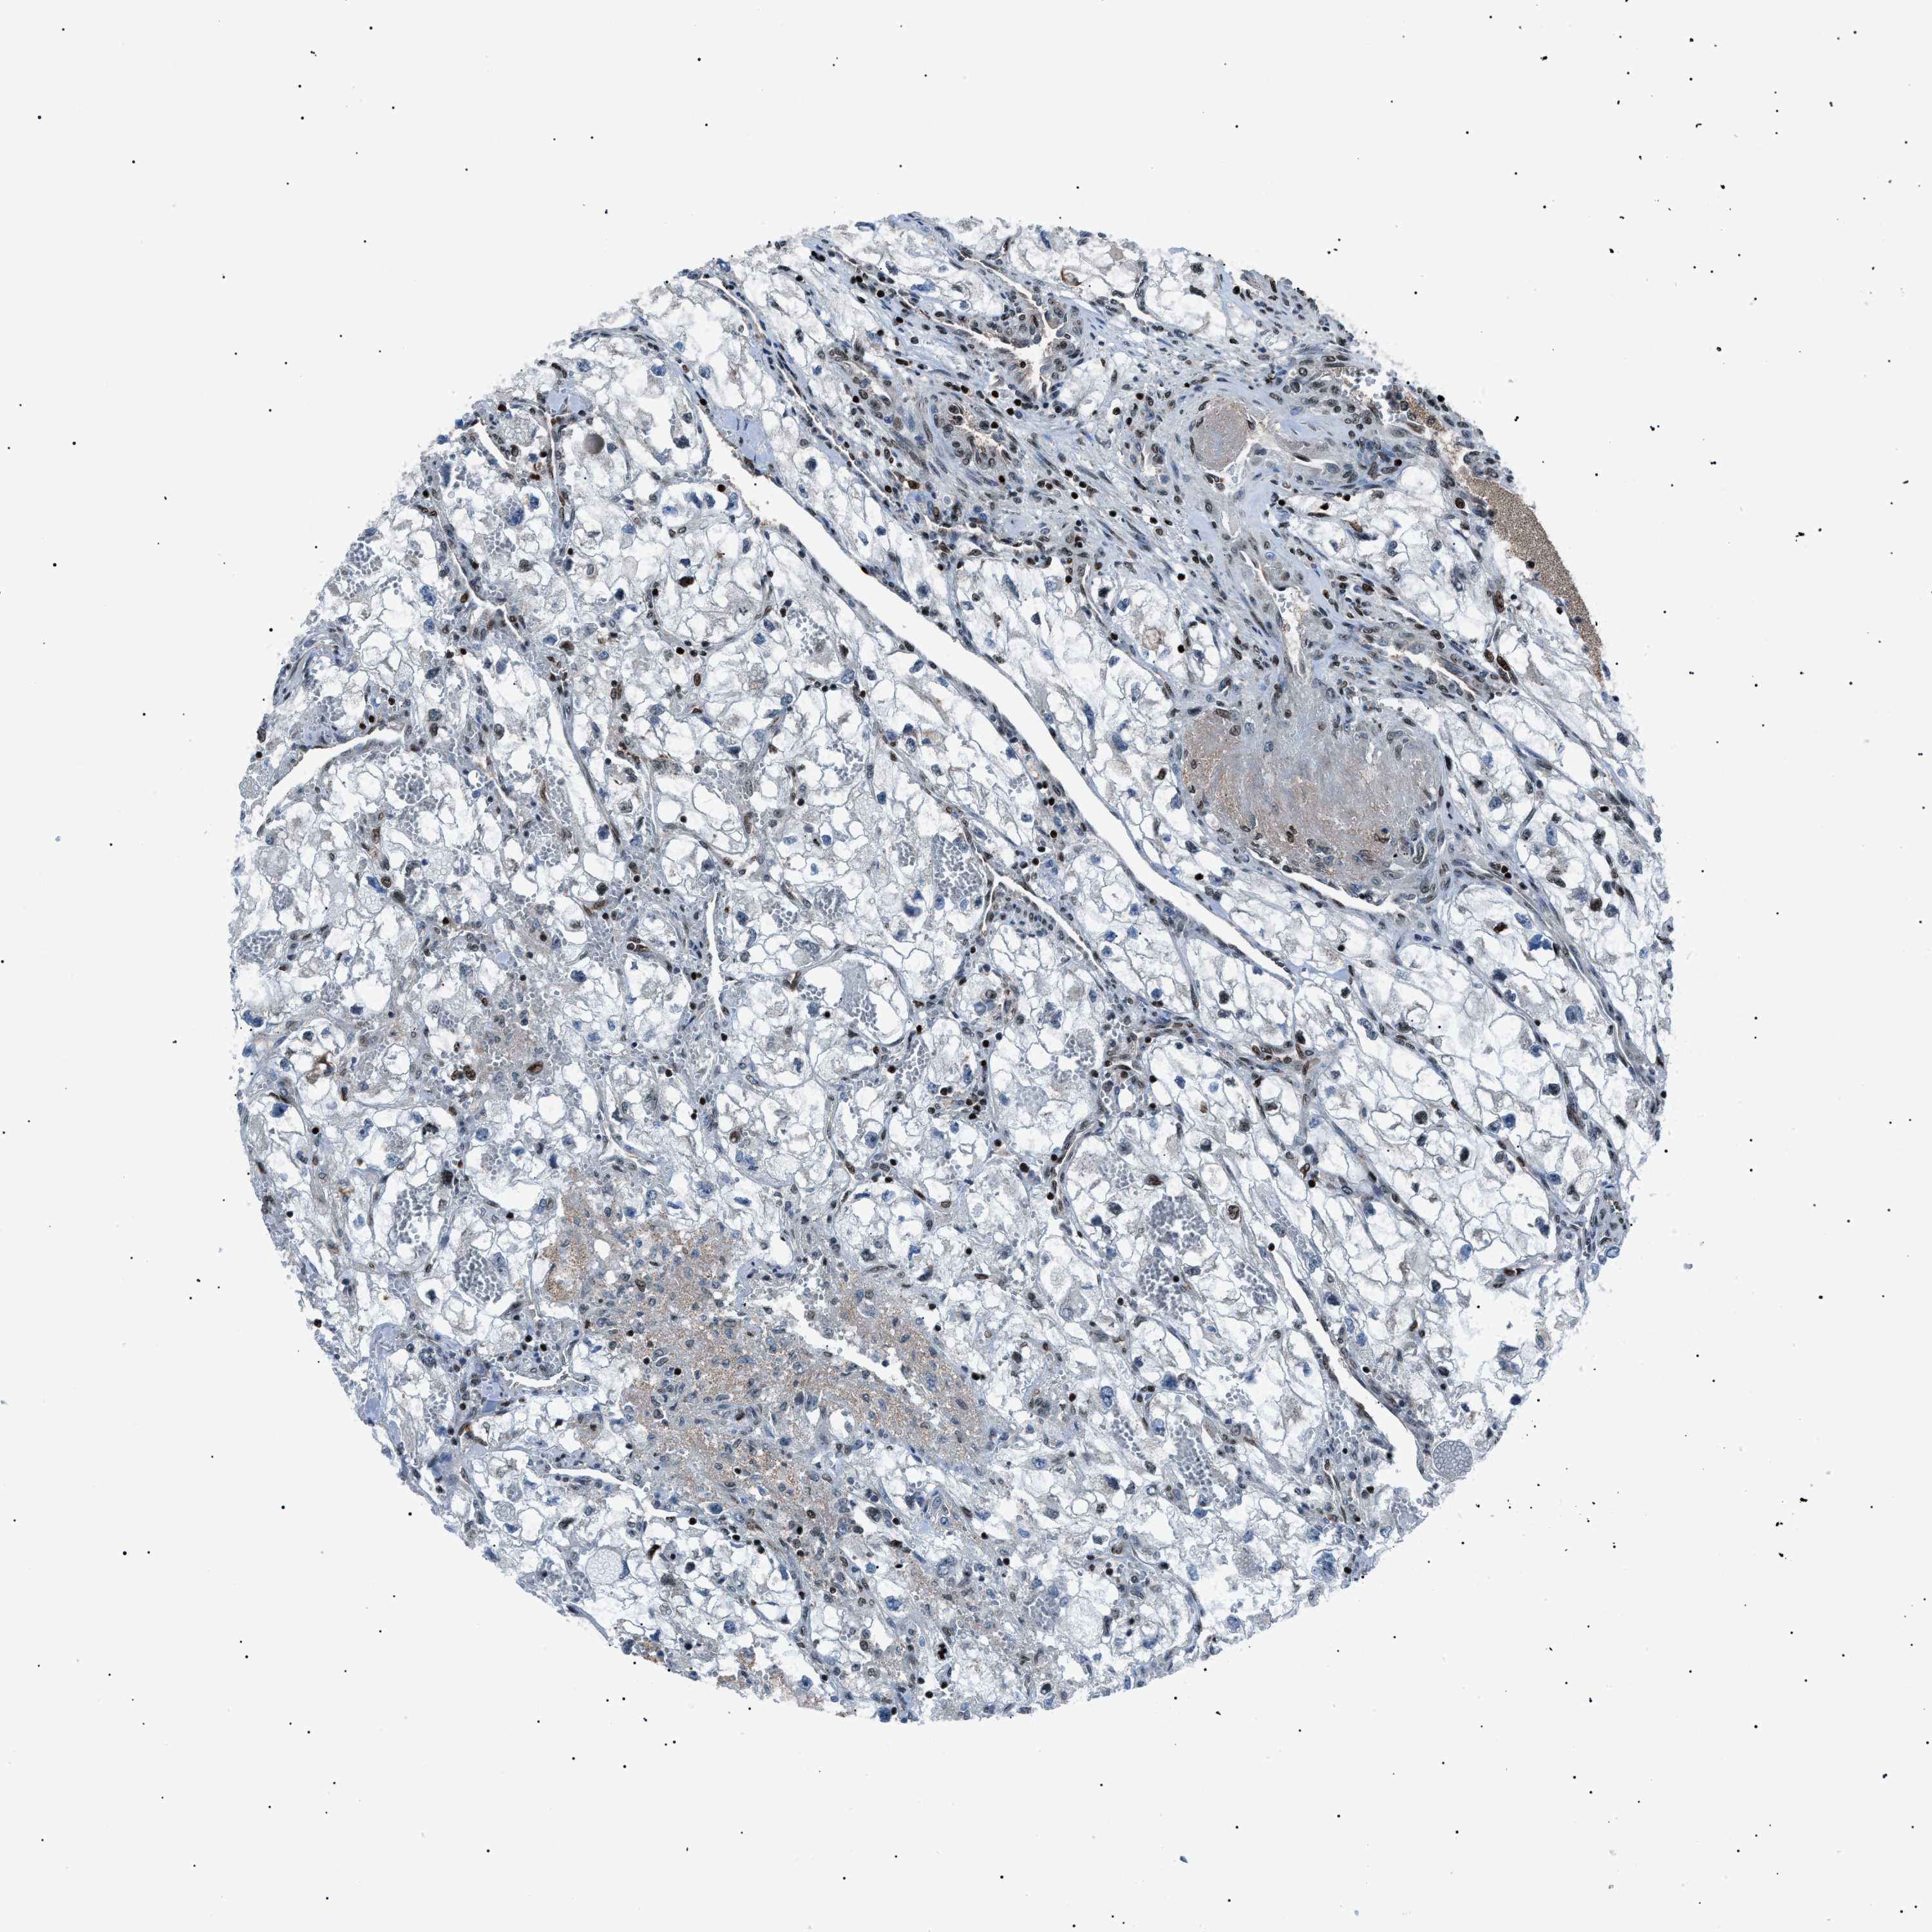

KIDNEY RENAL PAPILLARY CELL CARCINOMA (TCGA) - Interactive survival scatter ploti

The Survival Scatter plot shows the clinical status (i.e. dead or alive) for all individuals in the patient cohort, based on the same data that underlies the corresponding Kaplan-Meier plots. Patients that are alive at last time for follow-up are shown in blue and patients who have died during the study are shown in red.

The x-axis shows the expression levels (FPKM) of the investigated gene in the tumor tissue at the time of diagnosis. The y-axis shows the follow-up time after diagnosis (years). Both axes are complimented with kernel density curves demonstrating the data density over the axes. The top density plot shows the expression levels (FPKM) distribution among dead (red) and alive patients (blue). The right density plot shows the data density of the survived years of dead patients with high and low expression levels respectively, stratified using the cutoff indicated by the vertical dashed line through the Survival Scatter plot. This cutoff is automatically defined based on the FPKM cutoff that minimizes the p-score. The cutoff can be changed by dragging the vertical line or by entering a cutoff value in the square labeled "Current cut-off".

Under the Survival Scatter plot the p-score landscape (black curve; left axis) is shown together with dead median separation (red curve; right axis). Dead median separation is the difference in median mRNA expression between patients who have died with high and low expression, respectively. It is calculated as follows: median FPKM expression of dead patients with high expression - median FPKM expression of dead patients with low expression. This is intended to aid the user in visually exploring custom cutoffs and the associated p-scores and dead median separation.

Individual patient data is displayed and can be filtered by clicking on one or more of the category buttons on the top of the page. Categories describing expression level and patient information include: high, low, alive, dead, female, male and tumor stages. The scale of the x-axis can be toggled between linear and log-scale by clicking on the "x log" button. Mouse-over function shows TCGA ID, patient information and mRNA expression (FPKM) for each patient.

& Survival analysisi

Kaplan-Meier plots summarize results from analysis of correlation between mRNA expression level and patient survival. Patients were divided based on level of expression into one of the two groups "low" (under cut off) or "high" (over cut off). X-axis shows time for survival (years) and y-axis shows the probability of survival, where 1.0 corresponds to 100 percent.

PRKX is not prognostic in Kidney Renal Papillary Cell Carcinoma (TCGA)